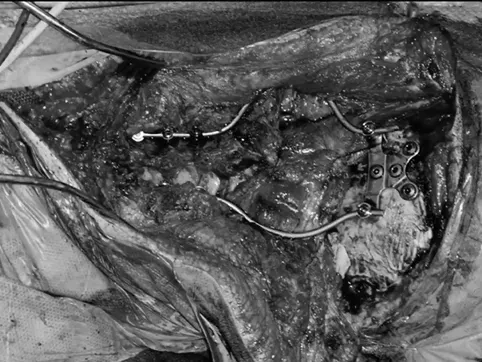

事实上,福教授在切除肿瘤后,还为杰森进行了枕颈固定融合术(occipitocervical fusion,OCF)。他在颈椎的C0、C3、C4和C5椎体上分别开孔,以便植入螺钉。

这些螺钉在设计上就十分巧妙,采用了曲线方式横向弯折,使其能够更好地适应颈椎的生理曲度。这种固定方式不仅能提高固定效果,还能减少对周围软组织的损伤。

在植入螺钉后,福教授还使用Roy-Camille技术将颈椎的C0-C5椎体进行融合,使用聚甲基丙烯酸甲酯(Polymethyl Methacrylate)材料填充椎体之间的空隙,以促进骨组织的生长和愈合,从而提升颈椎的稳定性。